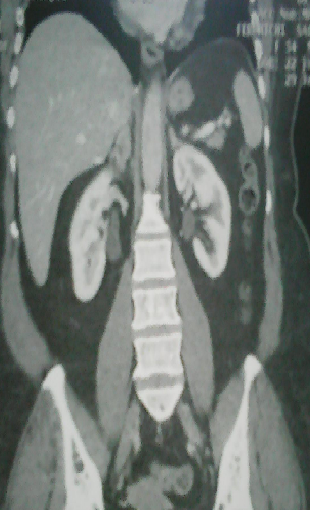

La tuberculose surrénalienne isolée est rare et de diagnostic difficile. Elle est parfois découverte à l'occasion d'une insuffisance surrénalienne. Des cas d'incidentalomes révélant une tuberculose surrénalienne primitive sont exceptionnels. Patient âgé de 42 ans sans antécédents particuliers ni notion de contage tuberculeux, a consulté pour des douleurs de l'hypochondre droit évoluant depuis un mois, une anorexie et un amaigrissement de 7 Kg sans fièvre ni troubles du transit. L'examen physique n'a pas objectivé de masse palpable ni d'hépato-splénomégalie. La tension artérielle était à 130/70 mmHg. L'examen biologique n'a pas révélé de syndrome inflammatoire, ni de signes de malabsorption. L'échographie et la TDM abdomino-pelvienne ont montré une hypertrophie de la surrénale droite sans adénopathies associées. Plusieurs diagnostics ont été évoqués tels qu'un lymphome, une tuberculose ou une néoplasie solide. Le dosage des hormones surrénaliennes était normal. L'intradermo-réaction à la tuberculine était fortement positive. Le Quantiféron test était positif. L'examen anatomopathologique a révélé des granulomes épithéloïdes et giganto-cellulaires avec nécrose caséeuse. Les autres localisations tuberculeuses partculièrement respiratoires, urinaires et digestives ont été éliminées. Le diagnostic de tuberculose surrénalienne droite isolée a été posé. L'évolution était favorable sous un traitement anti-tuberculeux (l'association isoniazide, rifampicine, éthambutol et pyrazinamide pendant deux mois puis l'association isoniazide et rifampicine pendant huit mois) bien conduit.